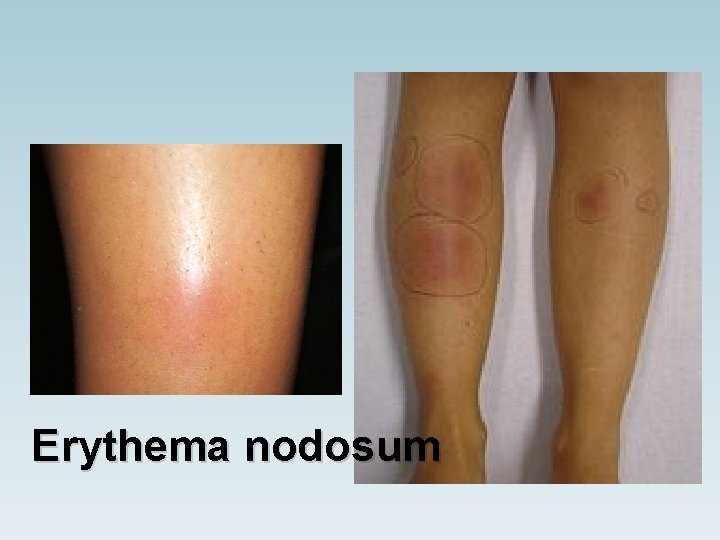

Hepatitis Palpable splenomegaly Chlamydia Endocarditis Stevens–Johnson syndrome Erythema nodosum

Erythema nodosum